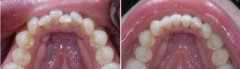

成功的美容修复怎么辨别?

美容修复能够快速矫正成人畸形牙、色素牙问题,因而受到万千美牙者的青睐,...【详细】